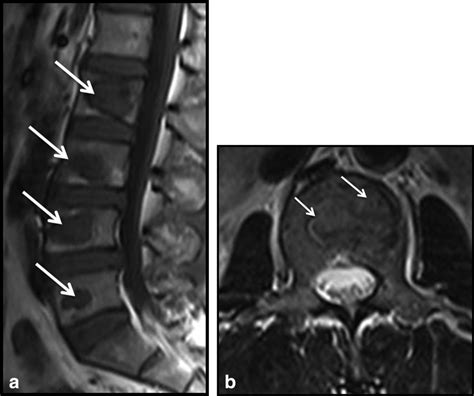

Diagnosis of spinal lesions typically involves a combination of physical examination, medical history, and diagnostic imaging tests, such as MRI or CT scans. A physical examination may reveal signs of spinal instability or neurological deficits, while a medical history may reveal a history of trauma, infection, or inflammation. Diagnostic imaging tests, such as MRI or CT scans, can help confirm the presence and location of spinal lesions, as well as the extent of any damage or inflammation.

Diagnostic imaging tests, such as MRI or CT scans, are used to confirm the presence and location of spinal lesions, as well as the extent of any damage or inflammation. MRI scans, for example, can provide detailed images of the spinal cord and vertebrae, while CT scans can provide images of the bony structures of the spine.